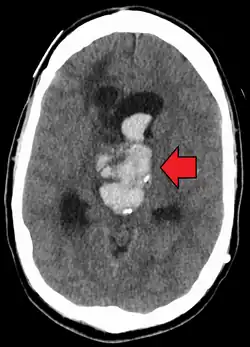

Axiali CT scan of a spontaneous intracranial hemorrhage | |

A non-contrast CT scan (computed tomography) of the brain is commonly used as the initial imaging modality in suspected cases of intracranial hemorrhage. CT is preferred in emergency settings due to its speed, availability, and high sensitivity for detecting acute brain injuries, enabling rapid triage and surgical decision-making. Examples of brain diseases that require urgent intervention are: large-volume hemorrhage, brain herniation, and cerebral infarction. Additional advantages of CT imaging include its effectiveness in detecting bony fractures, vascular injuries, and cerebrospinal fluid (CSF) leaks.

A swirl sign on CT imaging— representing areas of low density with surrounding areas of high density— suggest active intracranial bleeding. The presence of this sign is associated with an increase in risk of death within one month and a poor functional prognosis at three months among survivors.[6]